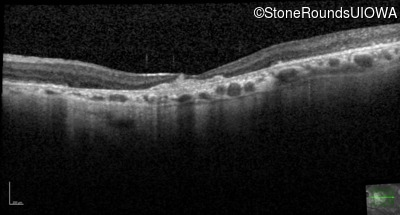

Optical Coherence Tomography - Right - 20/100

Exemplar / OCT Stack